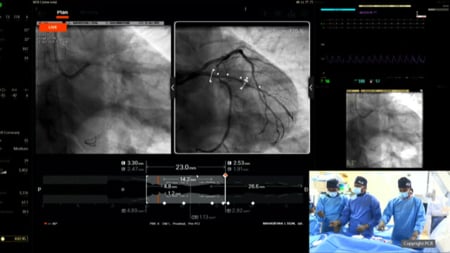

Precision PCI in the era of AI and multimodality imaging

Nailing the ostium of LAD, although technically challenging, can be precisely done with mandatory intracoronary imaging. It is essential to rule out disease extension into left main artery as, otherwise, cross over LM-LAD stenting strategy would be preferable. CTCA can help the interventionist plan the PCI,...